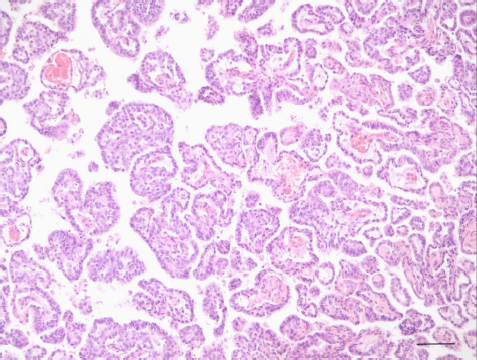

Histological examination described a nonencapsulated, moderately cellular, rather loose, proliferation of cuboidal to columnar epithelium breaching through chunks of an otherwise normal appearing dura mater and invading some cranial nerves. Cells were arranged in papillae, large cystic lacunae with low amount of faintly eosinophilic amorphous material, or glandular architecture, depending on the region considered (Fig. 3).

These cells were supported by a moderate amount of moderately vascularized stroma. Cells presented with moderate anisocytosis and mild anisokaryosis with variations in between cuboidal and columnar ciliated epithelium, mildly increased nucleus/cytoplasm ratio, and nonpolarized nuclei. There were 15 mitoses in 5 high-power fields. Immunohistochemistry for pancytokeratin displayed diffuse immunoreactivity of the proliferating cells (Fig. 4), also showing high ki67 positivity, while neuron-specific enolase and glial fibrillary acidic protein were negative. Sections of the cerebellum and brainstem revealed moderate, focal, impingement of the parenchyma with very mild extension of the proliferating cells into the ventral left side of the medulla oblongata. Very mild perilesional edema, mild multifocal microglial activation, and very mild diffuse astrocytosis and astrogliosis were detected at this level. Eosinophilic neuronal necrosis was also occasionally observed. Similar reactive changes of the neuroparenchyma were encountered along the ventral paramedian lobule and paraflocculus with no clear evidence of invasion by proliferating cells. Location, morphologic features, and immunohistochemical labeling were consistent with a diagnosis of ELST .

Fig. 3. ELST. Neoplastic cells grow forming papillary projections lined by one to two layers of polygonal cells and supported by a delicate fibrovascular stroma (H&E stain; scale bar=100 µm).